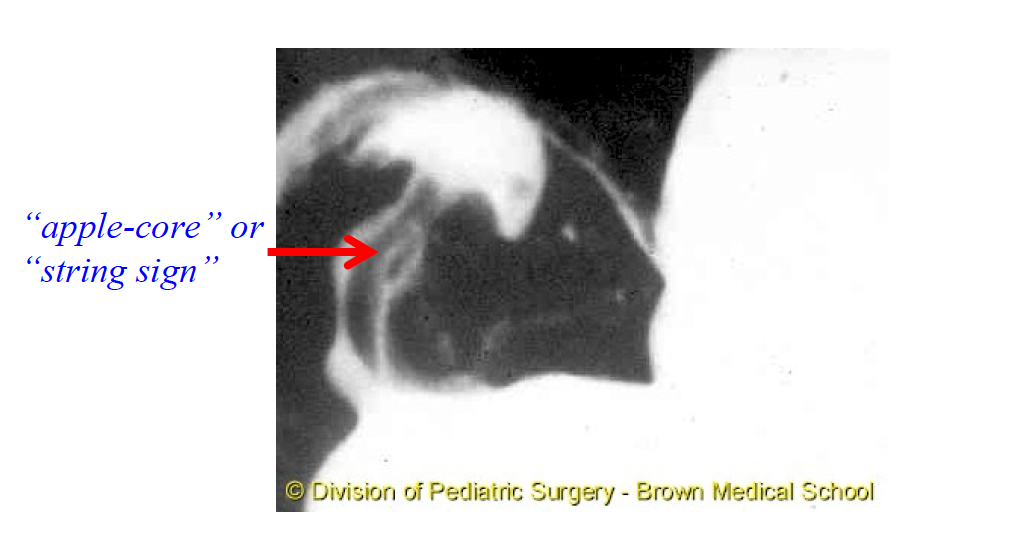

Q

Xray can be nonspecific for volvulus, but on barium what will you see that can be diagnostic.?

A

cecum in upper right quadrant and not lower right quadrant